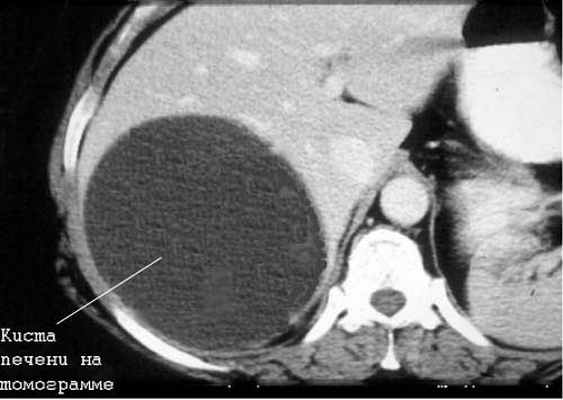

Киста печени

Чаще встречаются непаразитарные кисты. Учитывается возможность поликистозной болезни, а также солитарных и множественных истинных и ложных кист печени.

Большинство кист небольшие (диаметром 1-5 см), чаще встречаются у женщин. Значительная часть их имеет бессимптомное течение. У ряда больных отмечаются боли в правом подреберье, у одних — постоянные, у других — периодические. Существенную помощь оказывает использование УЗИ и КТ (или ЯМР), обладающие высокой разрешающей способностью. Необходимо учитывать возможность поликистоза печени.

Дифференциальная диагностика ДОП обычно начинается с исключения кист. Чаще встречаются непаразитарные кисты. Учитывается возможность поликистозной болезни, а также солитарных и множественных истинных и ложных кист печени.

Большинство кист небольшие (диаметром 1-5 см), чаще встречаются у женщин. Значительная часть их имеет бессимптомное течение. У ряда больных отмечаются боли в правом подреберье, у одних - постоянные, у других - периодические. Существенную помощь оказывает использование УЗИ и КТ (или ЯМР), обладающие высокой разрешающей способностью. Необходимо учитывать возможность поликистоза печени.